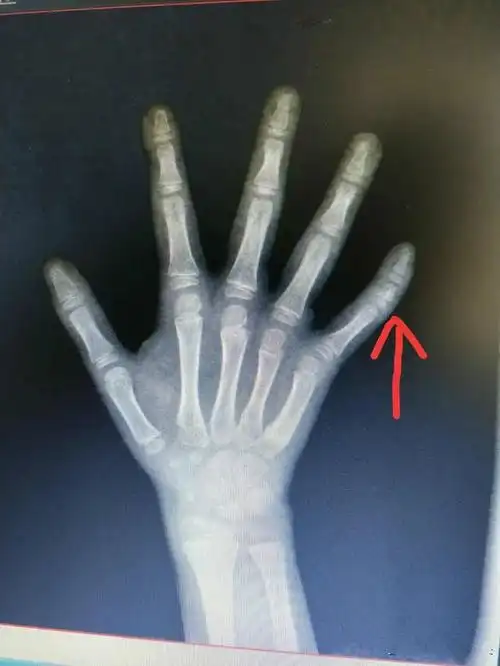

如何确诊指骨骨骺早闭?

长骨的最终长度也决定了成年后的身高,一般只要骨骺线未闭合,就还有